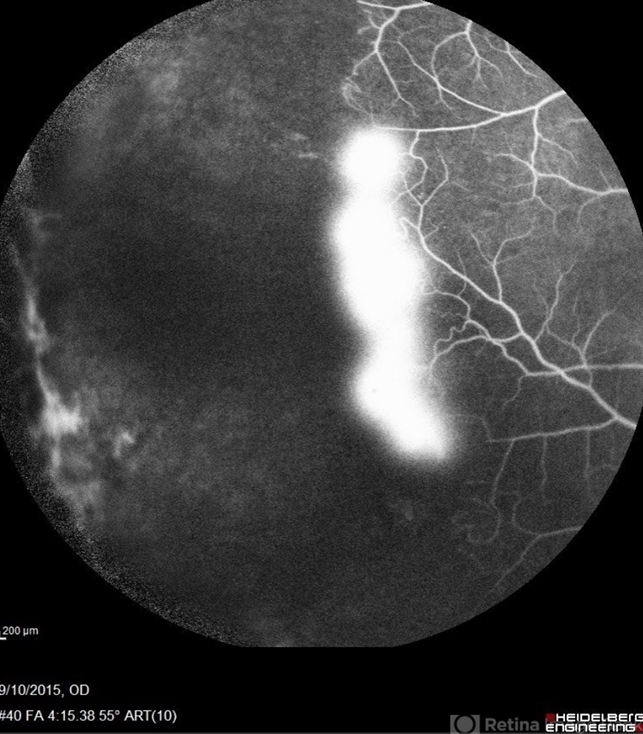

sickle cell retinopathy, peripheral retinal neovascularization, sea fan

Angiography showed normal vessels posteriorly but severe capillary drop out throughout the periphery OU with scattered severe neovascularization at the edge of the capillary drop out peripherally.